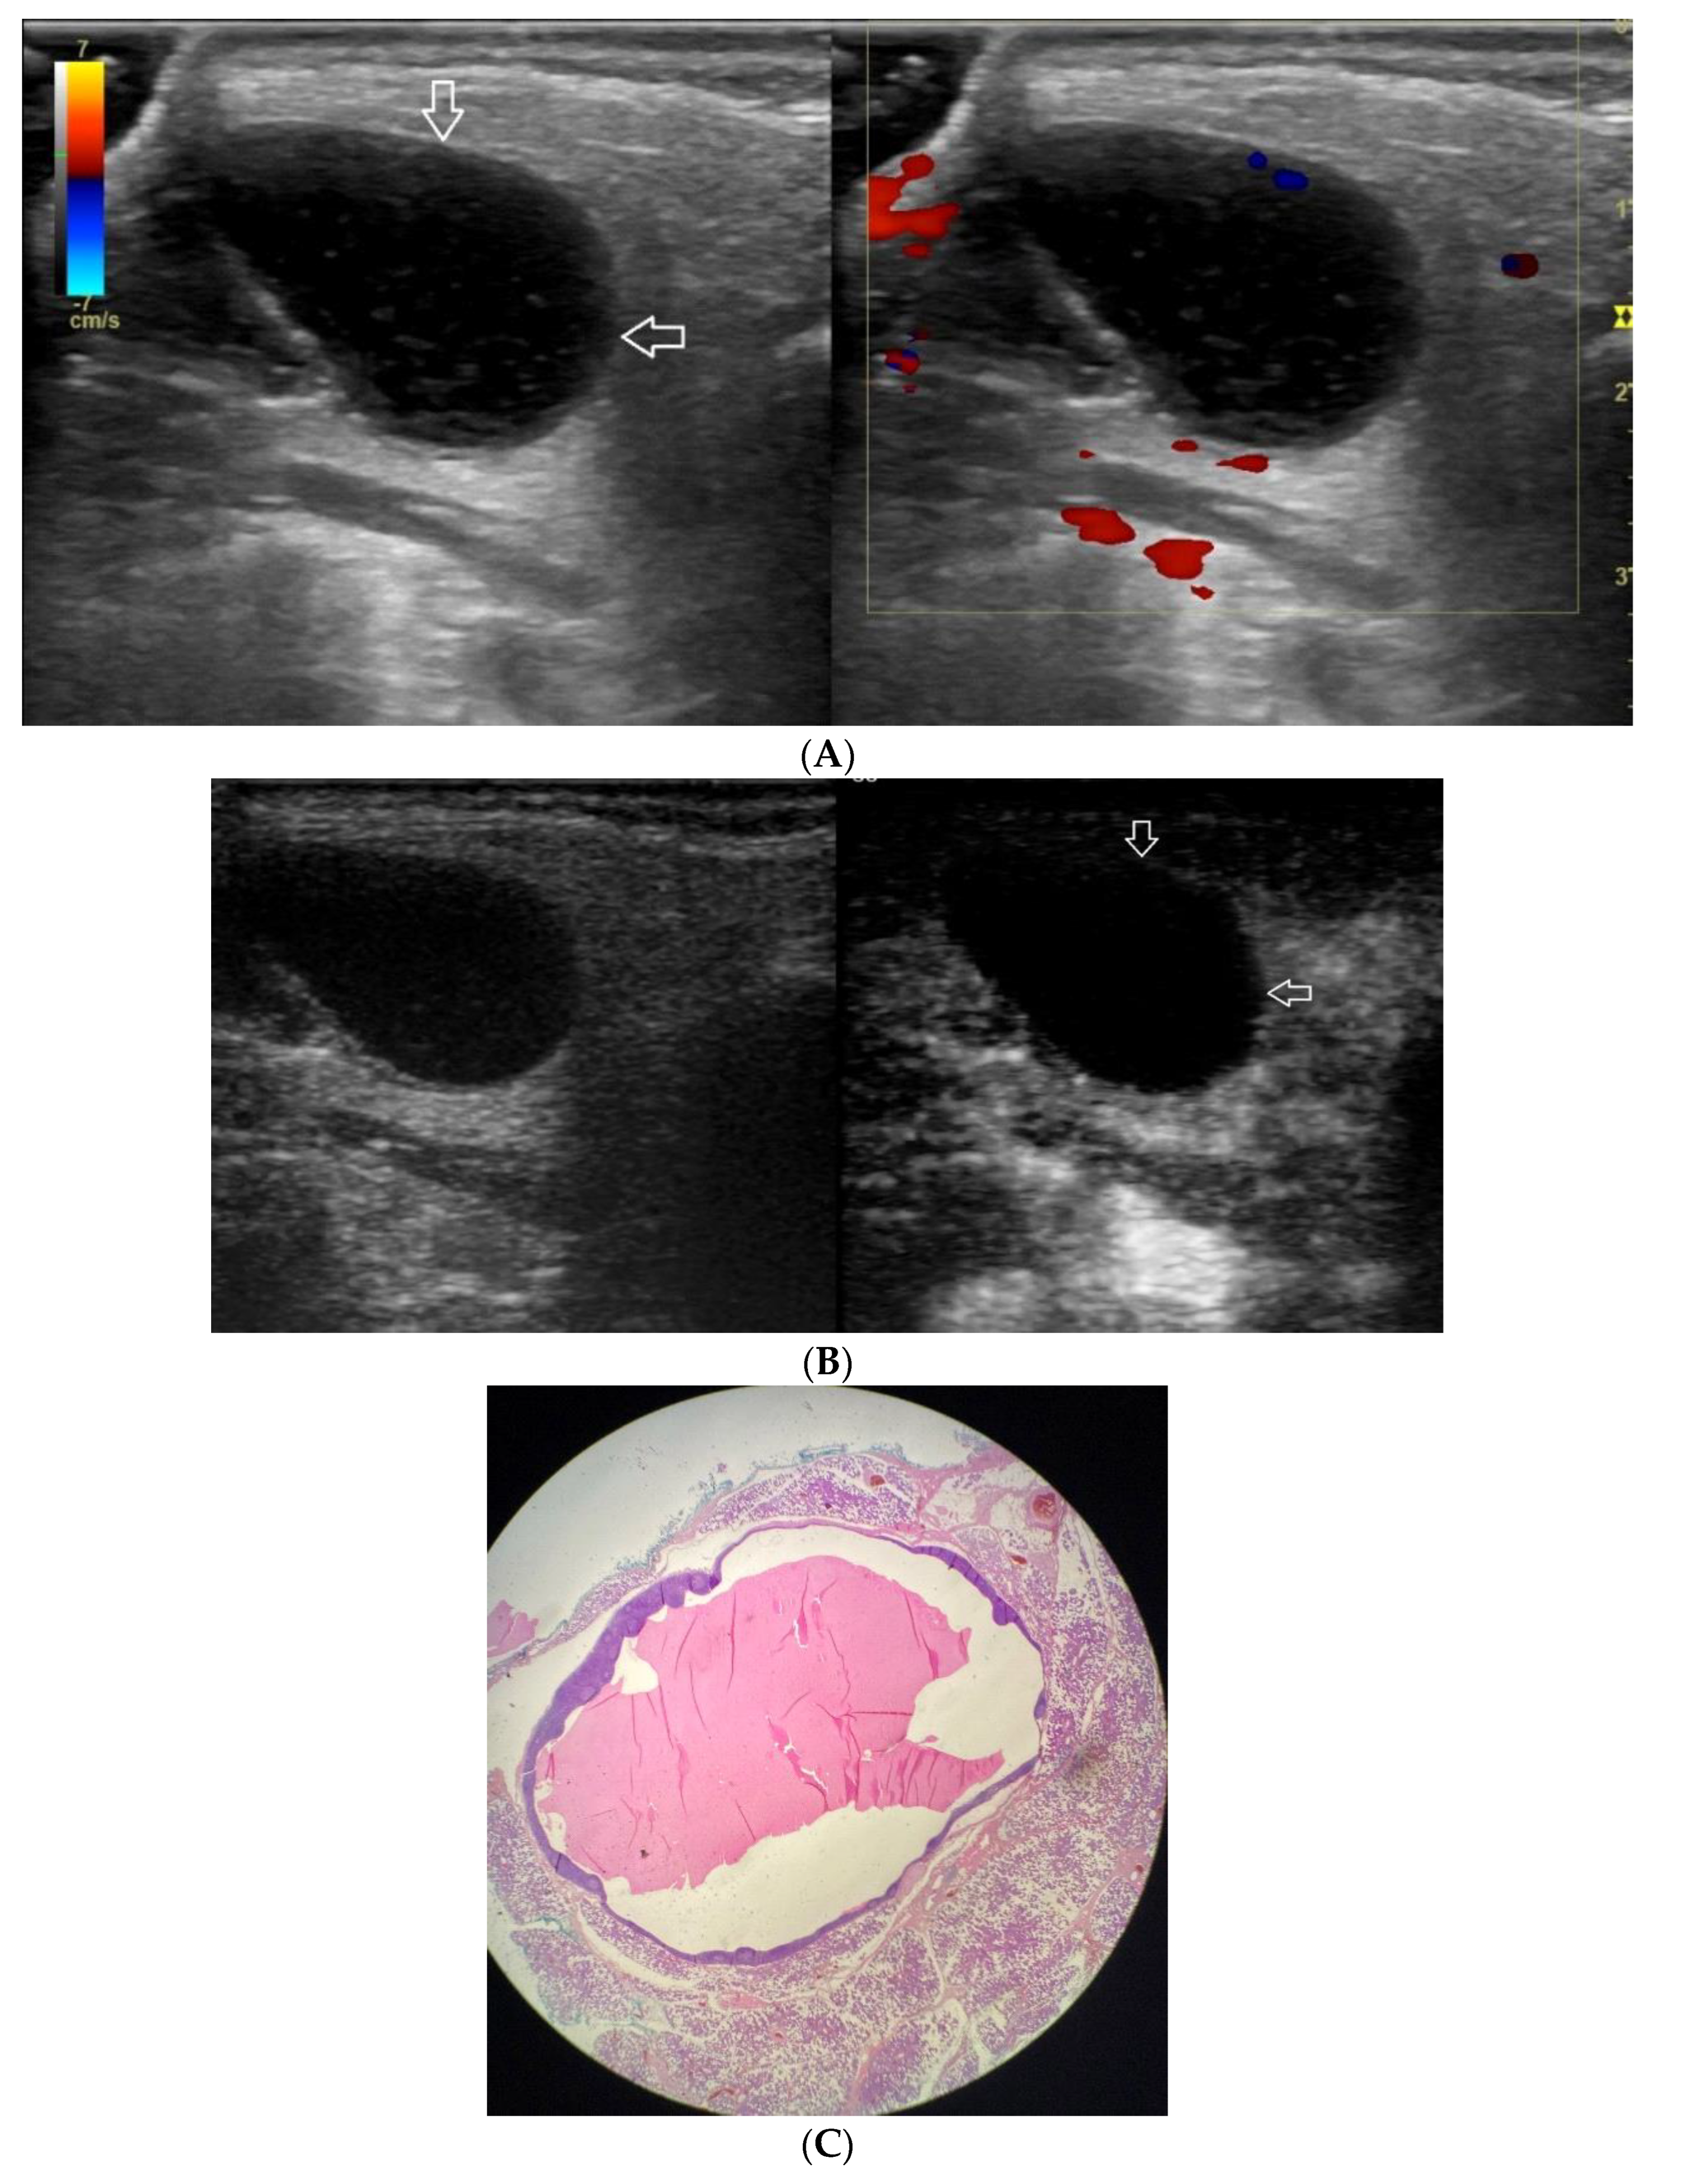

Figure 4.

(A−C) Warthin’s tumour. (A) Routine ultrasonographic examination in B presentation and colour Doppler: a big hypoechogenic well-demarcated focal lesion of a heterogeneous echostructure (white arrows). On CD, a low blood flow is observed. (B) Contrast-enhanced imaging in arterial phase: a strong homogeneous enhancement of a peripheral part of the lesion (white arrows). In the central part of the tumour, irregular areas without enhancement. (C) Pathomorphological image, H & E stain. Large areas of irregular shape containing fluid (white stars). A part containing glandular tissue located peripherally.

A correlation between professional photographs of CEUS imaging and those of microscope slides containing postoperative specimens was observed. It appears that the strong heterogeneous enhancement pattern is more likely to occur in benign lesions, while malignant, and malignant potential lesions tend to present weak heterogeneous enhancement. The foundation of such tendencies is revealed in pathomorphological specimens. Various tissues such as fluid and cartilage commonly present in salivary gland tumours, are generally poorly enhanced. The enhancement of such areas in CEUS is poor if any. The cross-section of Warthin tumour, for example, is presented by one or more often numerous minor cysts containing mucus.

Those not-enhanced areas and structures revealed on histopathological photographs overlapped (Figure 1, Figure 2, Figure 3, Figure 4, Figure 5 and Figure 6).